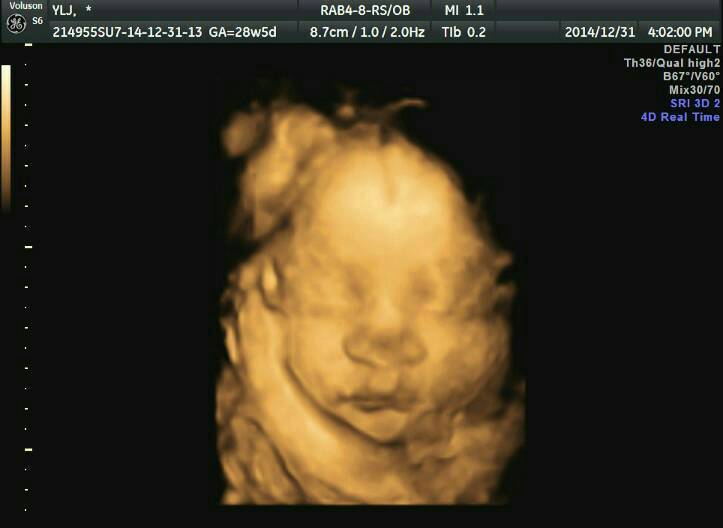

我的胎宝宝是塌鼻子吗?29周做了四维B超但医生只照了正面的脸部,发现宝宝鼻子又宽又塌感觉好丑的,可是我和宝爸的鼻子都不塌都是很挺的鼻梁,尤其是宝爸的鼻子又高又直非常帅!宝爸是我生命中唯一的男人,我的子宫没有被其他男人的精子污染过,宝宝当然没有其他男人的遗传基因。我家族中我爸的鼻子也是又高又直的,就是我妈的鼻子有一点塌其余几个舅舅全都是高鼻梁很帅气。难道说我宝宝长得随他外婆吗?(附上四维照片一张)

你好,现在宝宝还在发育阶段,还受到羊水等影响,目前五官看着部协调也是正常,就算是生下来的宝宝也是看不出随谁。宝宝的健康是最重要的,不要多想,安心养胎吧。